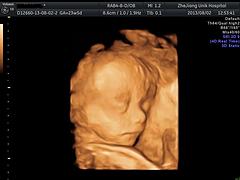

浙江优你可妇科门诊部有限公司是由有关部门核准登记注册的一家有限责任公司。在医疗保健服务行业经营许久,我们提供的三维彩超专业领先,效果显著,为广大孕妇带来了福音,并通过用心的服务,在浙江;全国地区建立了坚定的基础。我们有资深人士褚红女为您解答各类疑惑,欢迎来询。联系电话:18969036826

随着三维彩超市场竞争愈发的激烈。我司一直追求着“以人为本”的服务理念。为了消费者更加的轻松便捷,采用了电话预约的预约方式。我们的服务为广大的孕妇营造了良好的追求健康的氛围,让众多客户在我们这感受到宾至如归的感觉。

以三维彩超为主要业务,浙江优你可妇科医院的诚信、实力和服务均获得业界的认可,在公司全体员工的不懈努力下,在广大客户的支持下,浙江优你可妇科医院得到了长足的发展,受到了广大群众的欢迎。

针对我公司提供的三维彩超服务,以项目计费是我们一贯的收费标准,您可通过现结方式进行费用支付。为了能更好的为广大孕妇提供更便捷快速的三维彩超服务,您可以采用电话预约服务。